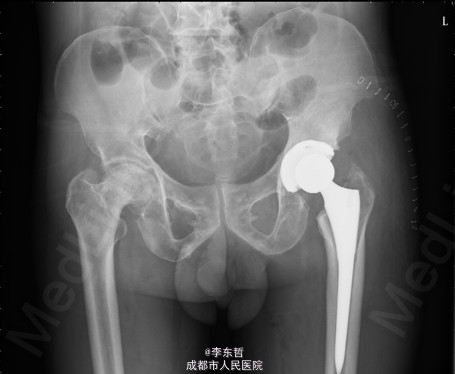

患者男,62岁,因“双髋疼痛4年,加重伴活动受限1年”入院。病员诉入院前4年无明显诱因出现双侧髋部疼痛,行走后疼痛加重,疼痛能忍受,双侧髋部无红肿,皮温不高,无畏寒、发热,休息后疼痛能自行缓解,无夜间疼痛,在当地医院行止痛药内服、理疗治疗,疼痛稍缓解。逐渐加重,1年前双侧髋部疼痛、跛行明显加重,左髋活动受限,行走困难,给予对症治疗症状无明显改善,遂到我科门诊就诊,X线片提示:双侧股骨头坏死,建议手术治疗,故于今日以“双侧侧股骨头坏死”收入我科进一步治疗。

查体:生命体征平稳,心肺腹未见异常;跛行,双左下肢较右下肢短缩1cm,左、右腹股沟中点深压痛,左、右髋叩击痛,左髋屈20°,伸0°,外展10°,内收10°,右髋屈60°,伸0°,外展20°,内收20°。双髋内、外旋活动受限,诱发疼痛,左侧重。 辅助检查:x线片示双侧股骨头坏死、塌陷变形,左侧明显,左髋半脱位。

初步诊断:1、左侧股骨头坏死伴内收肌挛缩(Ficat IV期);2、右侧股骨头坏死(Ficat IV期);3、右膝骨关节炎伴外翻畸形;入院后积极完善术前检查及准备,择期行手术治疗。